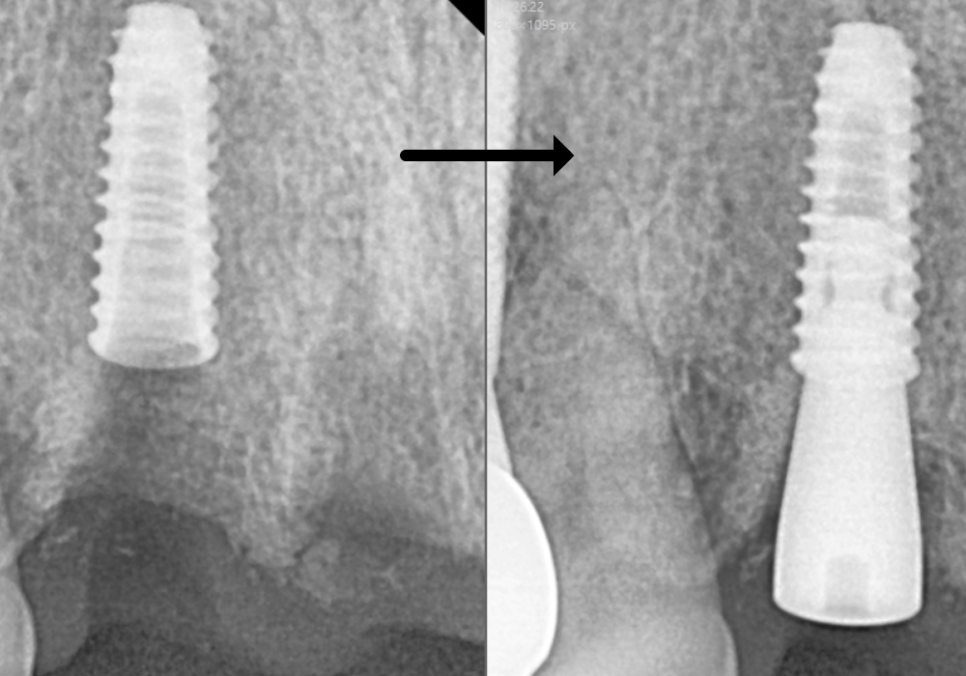

250531 기존 임플란트 크라운 제거 후 힐링(단추)으로 바꾼 모습

오른쪽 앞니(#12)인 기존 임플란트와

왼쪽 앞니(#22 )에 임플란트 식립하여

브릿지로 연결하는 방향으로

설계를 조정했습니다.

감액기간이지만 임플란트는

보장 50% 범위에서 진행을 도와드릴 수 있었고

뼈이식 내용도 보장되어,

필요 서류를 준비해 드린 덕분에

뼈이식 부분 또한 같이 보장받으셨습니다.

무엇보다 임플란트 1개를 추가로

식립하는 비용 부담을 줄이는 데

도움이 됐습니다.

250106 (전) 250626 (후)